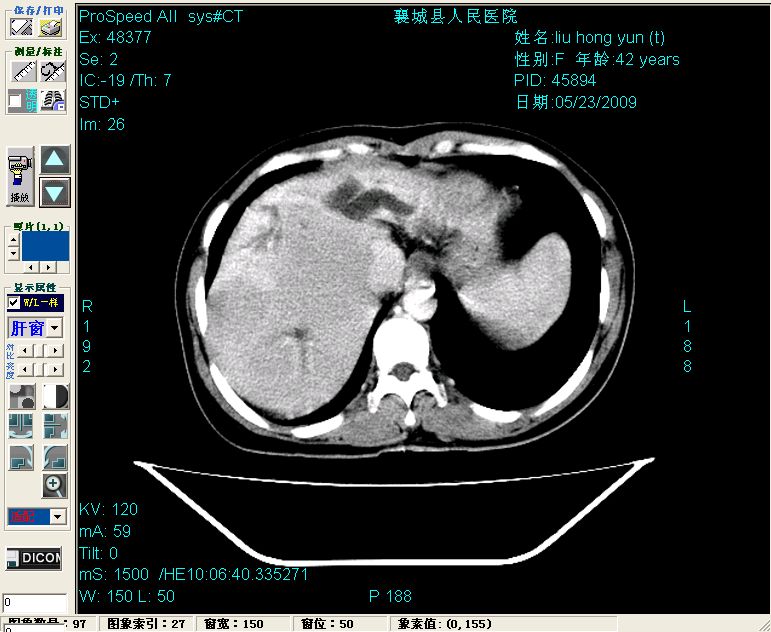

增强:

增强动脉期前述低密度区轻度早其强化,门脉期强化程度显著增高,延期扫描强化程度下降,但仍为相对高密度影

2左肝及右肝前叶表现考虑胆囊摘除术后所致的肝动门脉瘘形成,慢性纤维组织炎性增生.不完全除外左肝胆管细胞癌

1)肝内胆管结石,胆总管末端结石伴肝内胆管扩张。2)肝左叶及肝右叶前段增强前后之异常表现,考虑炎性改变,不排除胆管细胞癌。

1)肝内胆管结石,胆总管末端结石伴肝内胆管扩张。2)肝左叶及肝右叶前段增强前后之异常表现,考虑炎性改变,不排除胆管细胞癌。3)脾大。